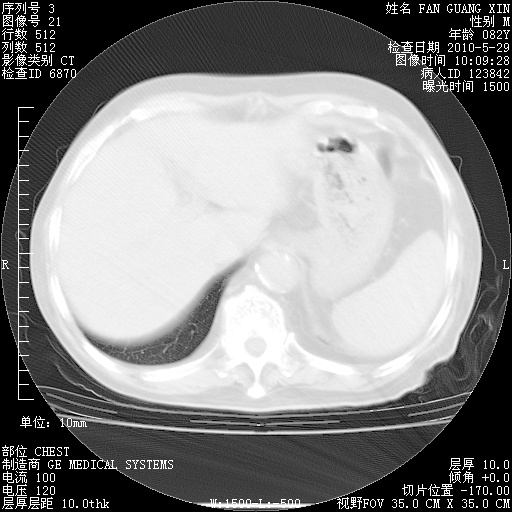

再治疗10天后的肺部CT

再治疗10天后的肺部CT 纵膈窗

从白细胞总数和中性比例看好像合并感染。肺部纹理好像比上次多,支气管炎?其他感染?

阅读此次胸部CT,肺间质渗出性改变较入院时有吸收。目前从体温、白细胞、中性分叶明显增高,肯定存在细菌感染(发生医院感染哦,若无消化道及泌尿系统等感染的依据,肺部感染可能大)。若你院头孢哌酮舒巴坦钠耐药率较高,同意你的方案,若48小时体温仍高,可考虑使用碳青霉稀类抗菌药物,同时可予超声雾化、注意滴数时加大液体量。白蛋白33.30g/L较低哦,需加强营养等支持治疗。